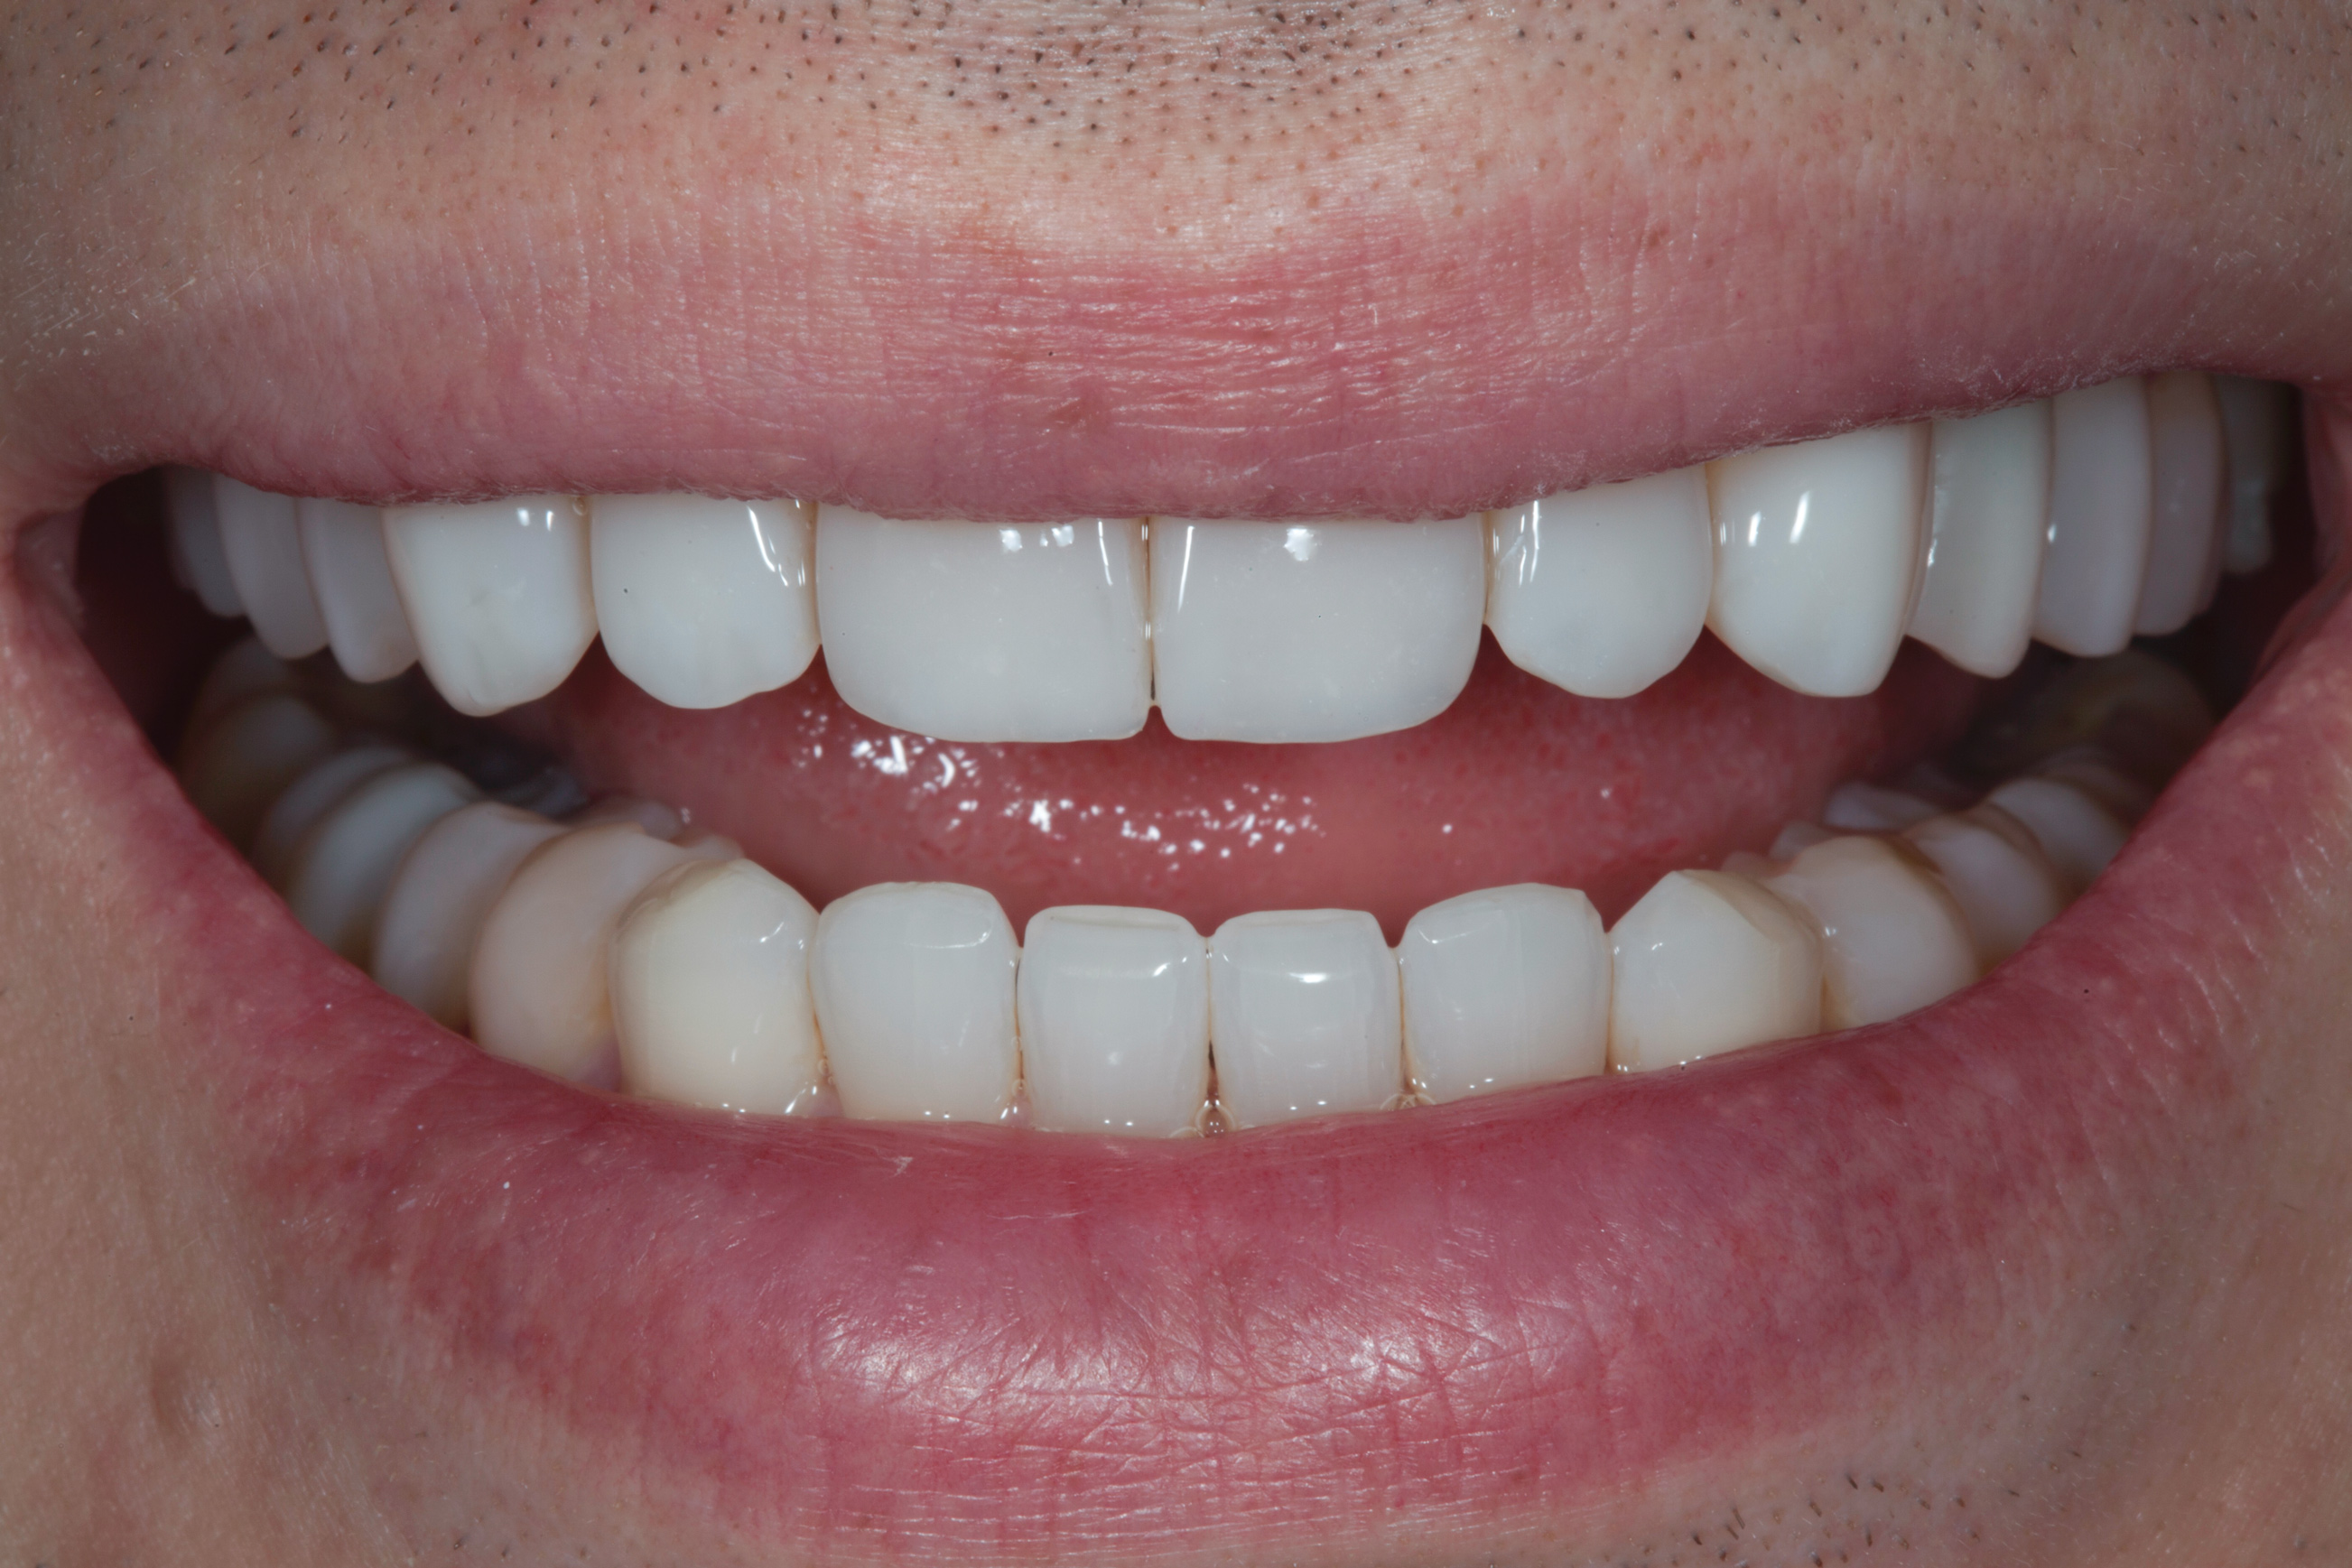

(10.) Postoperative smile photograph.

Figure 10

After the composite veneers were finalized, impressions were taken for a monolithic lithium disilicate crown on tooth No. 12. This was placed during a subsequent appointment, and occlusal equilibration was carried out. The patient returned for final photographs a couple of weeks later (Figure 10 through Figure 14).

Once the primary anatomy was finished, secondary anatomy was created by first marking off the desired position of developmental grooves with pencil and then placing them carefully with a flame-shaped diamond bur and abrasive points. The patient was also fitted with a bleaching tray for the lower arch and instructed to bleach only the lower anterior teeth.

The final polish was performed using a series of fine grit discs in various sizes, and a glass-like luster was achieved by applying aluminum oxide polishing paste with felt discs and points under light pressure.